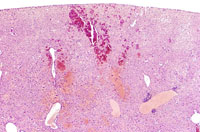

Angiectasis (peliosis hepatis, telangiectasis) is an incidental finding occasionally noted in aging mice. In extensive lesions, atrophy of adjacent hepatocytes may be seen. The lesions consists of dilated sinusoidal spaces lined by normal endothelial cells and filled with blood cells in immersion-fixed specimens. This lesion is occasionally associated with hepatocellular neoplasms. Angiectasis typically consists of smaller blood channels than is seen in hemangiomas. Also, angiectatic vascular channels are often not associated with endothelial cell proliferation as is seen in hemangiomas.

These examples represent low magnification views of angiectasis.